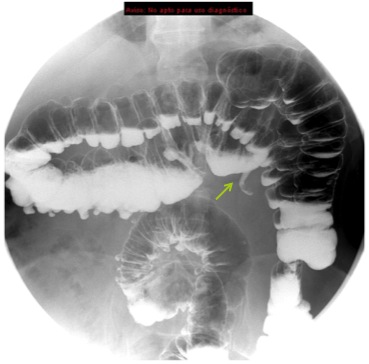

Se revisarón estudio previos, en un enema baritado y TC se observó:

Enema baritado con ciego (con apéndice visible) en posición anómala, localizado en hipocondrio izquierdo. TAC de adomen con signo de remolino o Twister de vasos. Otro hallazgo sería encontrar la VMS a la izquierda de la AMS.

Diagnóstico: MALROTACIÓN INTESTINAL.